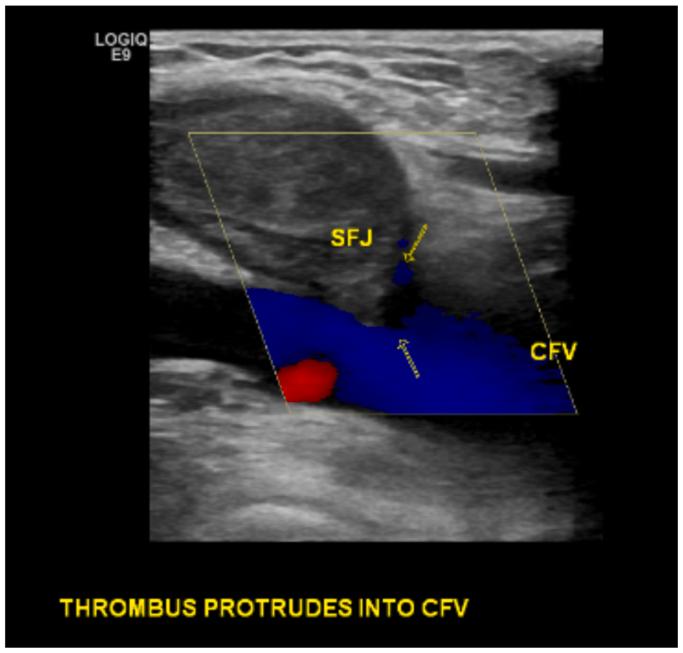

The reported incidence of pulmonary embolism in the published literature after radiofrequency ablation of the great saphenous vein is exceedingly rare. Recent societal clinical practice guidelines recommend against routine postprocedural ultrasound screening for ablation-related thrombus extension in asymptomatic average-risk patients. However, screening is recommended for asymptomatic high-risk patients. We present the case of a 69-year-old woman with multiple risk factors for the development of venous thromboembolism who developed bilateral pulmonary emboli despite early postprocedural ultrasound screening. As highlighted in this paper, surveillance ultrasound cannot be solely relied upon to detect and prevent pulmonary embolus after great saphenous vein radiofrequency ablation.

已发表文献中报道的大隐静脉射频消融术后肺栓塞的发生率极低。近期的社会临床实践指南不建议对无症状的平均风险患者进行常规术后超声筛查以检测消融相关血栓扩展。然而,建议对无症状的高风险患者进行筛查。我们报告一例69岁女性病例,该患者有发生静脉血栓栓塞的多种风险因素,尽管术后早期进行了超声筛查,但仍发生了双侧肺栓塞。如本文所强调,大隐静脉射频消融术后不能单纯依靠监测超声来检测和预防肺栓塞。